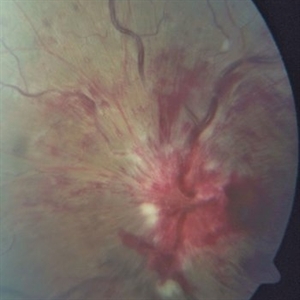

Traumatic optic nerve avulsion

Apr 23 2015 by Mehul A Shah

30-year-old male presented with blunt ocular trauma following vehicular accident, and lost vision on examination fundus picture is displayed in image.

Photographer: Mehul Shah, Drashti Netralaya

Imaging device: Zeiss FF450plus

Condition/keywords: optic nerve head avulsion, traumatic optic neuropathy